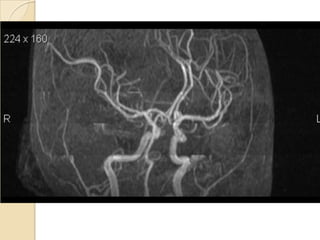

Arteries of the brain (lateral view) - MRA

1. Anterior cerebral artery

2. Anterior communicating artery

3. Basilar artery

4. branches (in insula) of middle cerebral artery

5. Cavernous portion of internal carotid artery

6. Cervical portion of internal carotid artery

7. Genu of middle cerebral artery

8. Intracranial (supraclinoid) internal carotid artery

9. Middle cerebral artery

10. Ophthalmic artery

11. Petrous portion of internal carotid artery

12. Posterior cerebral artery

13. Posterior cerebral artery in ambient cistern

14. posterior cerebral artery in interpeduncular

cistern

15. Posterior communicating artery

16. Posterior inf cerebellar artery.

17. Quadrigeminal portion of posterior cerebral

artery

18. Superior cerebellar artery

19. Vertebral artery